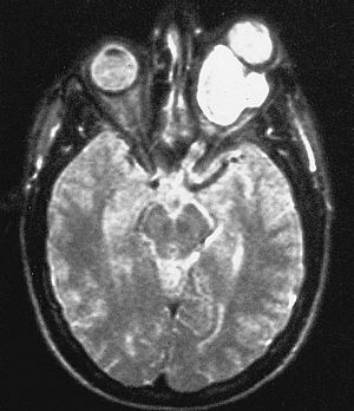

INC國(guó)際神經(jīng)外科專家指出,雖然視神經(jīng)膠質(zhì)瘤通常被歸類為良性的低等級(jí)WHO(國(guó)際衛(wèi)生組織)1級(jí)毛細(xì)胞星形細(xì)胞瘤,一般很少進(jìn)展到高等級(jí)。但視神經(jīng)膠質(zhì)瘤由于生長(zhǎng)在視神經(jīng)上,隨著緩慢的增大,會(huì)不斷影響孩子的視力,較終可能導(dǎo)致失明。視神經(jīng)型膠質(zhì)瘤在臨床上典型的表現(xiàn)為早期出現(xiàn)視力逐漸下降、視野缺損,隨著病變體積增大,出現(xiàn)眼眶占位性病變的特點(diǎn),即進(jìn)行性眼球突出、眼球運(yùn)動(dòng)受限、斜視等,故視力下降先于眼球突出出現(xiàn)。在嬰幼兒期的視神經(jīng)膠質(zhì)瘤多表現(xiàn)為眼球震顫和斜視。特別是兒童出現(xiàn)視力下降時(shí)因其主訴不明確,往往在出現(xiàn)明顯的眼球突出或因視力喪失導(dǎo)致廢用性斜視時(shí)被家長(zhǎng)發(fā)現(xiàn)才就診,故兒童患者就診時(shí)視力損傷已很嚴(yán)重甚至失明。